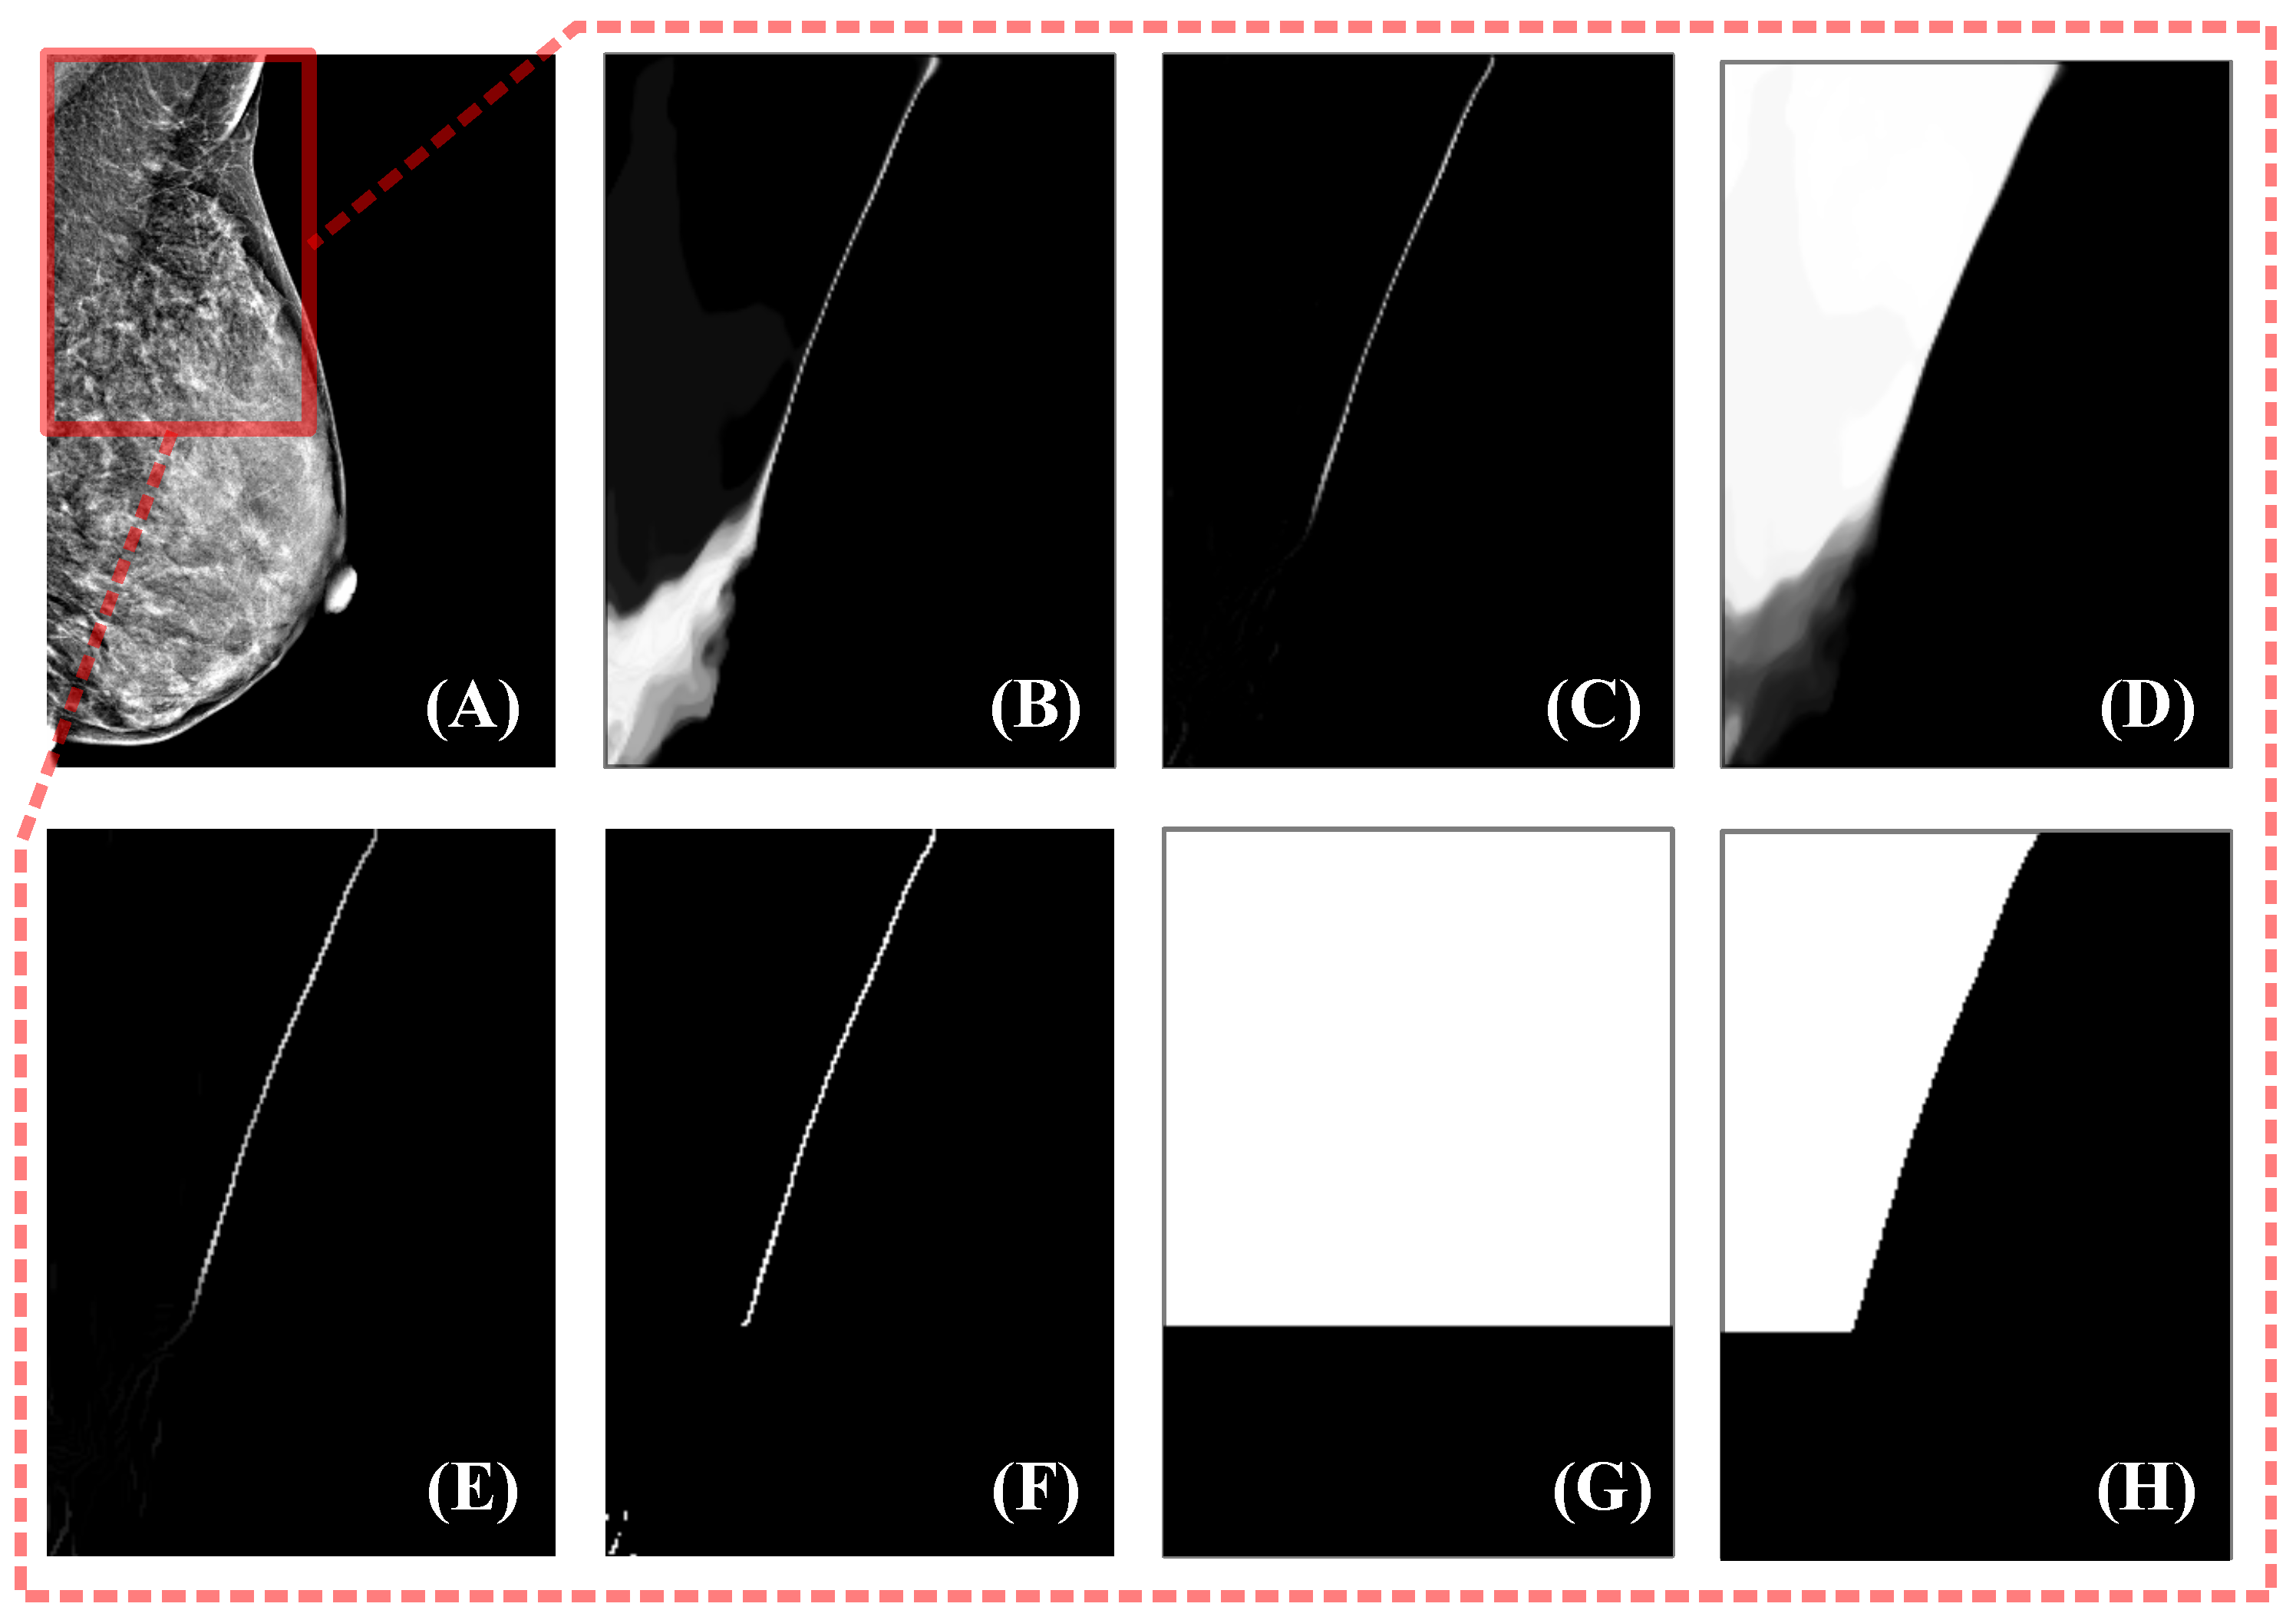

- The task of pectoral muscle segmentation can be split into two subtasks: detection of visible parts and estimation of invisible parts. The above methods only optimize for the final segmentation results, and the degree of optimization of the two tasks is difficult to balance during the training process. In most mammogram datasets, most images have a clear pectoral boundary, and the network tends to learn how to detect visible parts and ignore how to estimate blurred or missing parts. The performance of the model completely depends on the proportion of different types of data and the training tricks used, without addressing the problem through method design.

2.3. Uncertainty Estimation

2.4. Low-Confidence Prediction Refinement